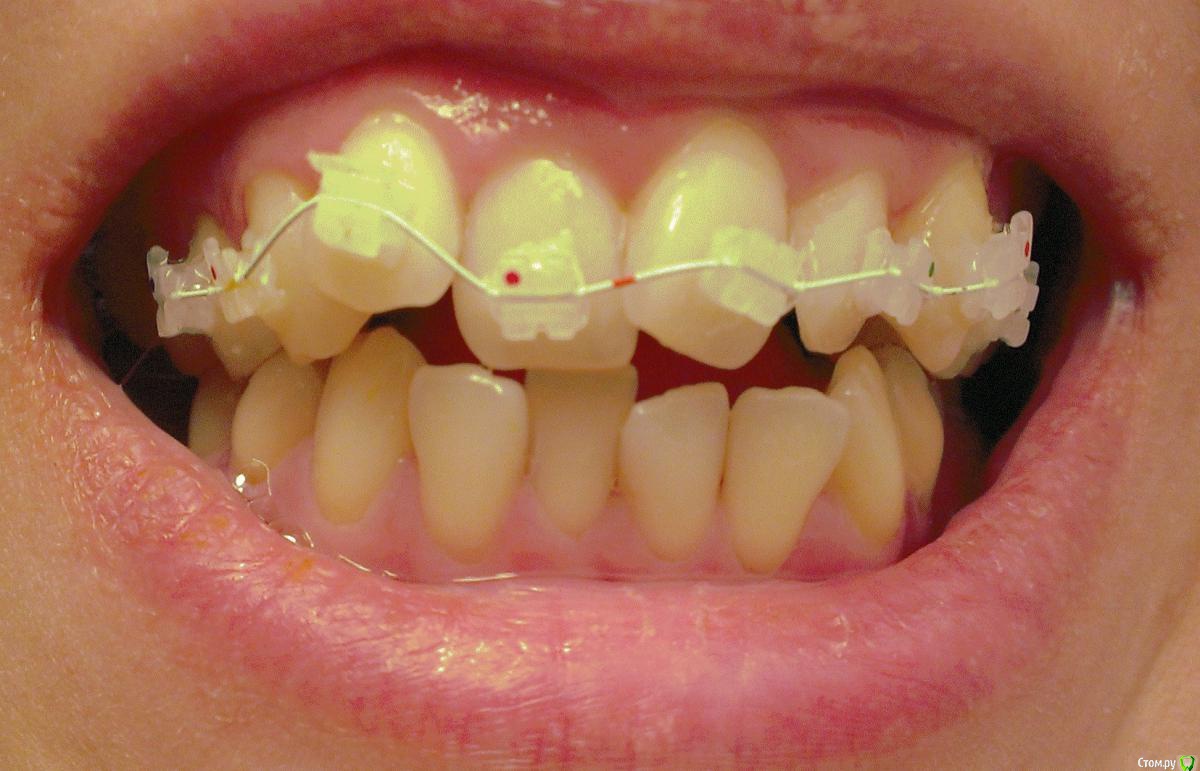

viktori Опубликовано 23 ноября, 2015 Поделиться Опубликовано 23 ноября, 2015 (изменено) Добрый день.Пожалуйста посоветуйте. Мне пять дней назад установили брекеты на верхнюю челюсть, но только на 8 зубов, до 5-ки, на обеих пятерках стоят коронки, одна временная специально для установки брекетов. Скученность зубов сильная, но врач сказал, что у меня там от пятерки и дальше все нормально и поэтому не надо на них ставить брекеты, я очень переживаю, так как читала, что должен формироваться прикус и поэтому все зубы должны быть выровнены, а в моем случае еще и нет места для выравнивания зубов если не двигать все, подскажите, есть ли такая практика и возможно ли выравнивание зубов если брекеты будут установлены только на 8 зубов.Дополнительно прикрепляю снимок. Изменено 23 ноября, 2015 пользователем viktori Ссылка на комментарий

Caries Опубликовано 26 ноября, 2015 Поделиться Опубликовано 26 ноября, 2015 Фиксация частичной аппаратуры приведет к работе в области задействованных зубов. При этом перемещение зубов будет непредсказуемым. Нужен анализ моделей челюстей, фотографий, рентгеновских снимков и потом лечение брекет-системой...полноценной Ссылка на комментарий